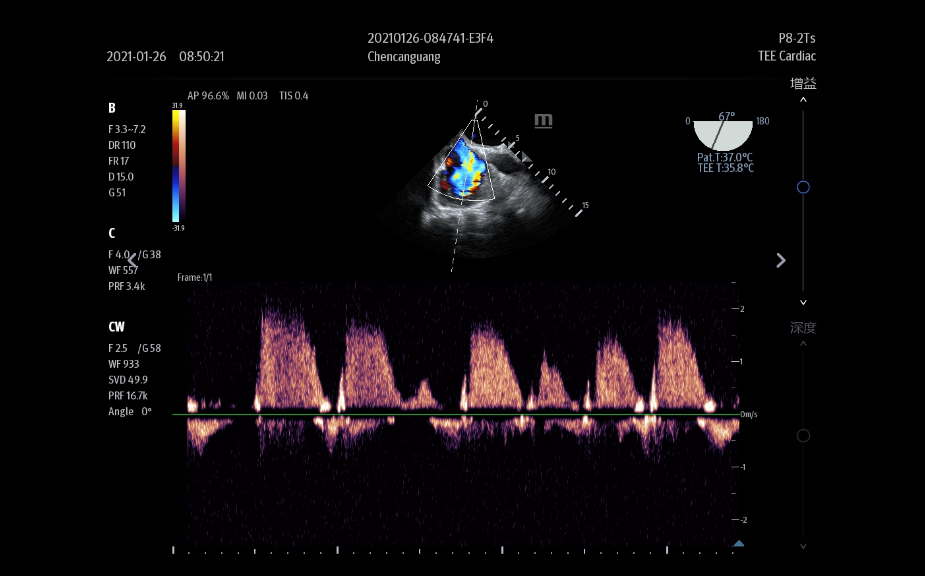

TE9

VisiĂłn ampliada, posibilidades ilimitadas

El sistema de ultrasonido TE9 estĂĄ dise?ado para ayudar a facilitar una mejor atenciĂłn al paciente y ampliar las capacidades de imagen para aplicaciones de anestesia, emergencias y cuidados crĂticos. Con funciones avanzadas, una gran pantalla tĂĄctil y una tecnologĂa de imagen superior, el TE9 es ideal para ayudar a mejorar la eficiencia clĂnica y la confianza en el diagnĂłstico. Las herramientas de automatizaciĂłn inteligentes brindan mediciones rĂĄpidas y reproducibles para exĂĄmenes y procedimientos fiables, incluso en entornos de gran presiĂłn.